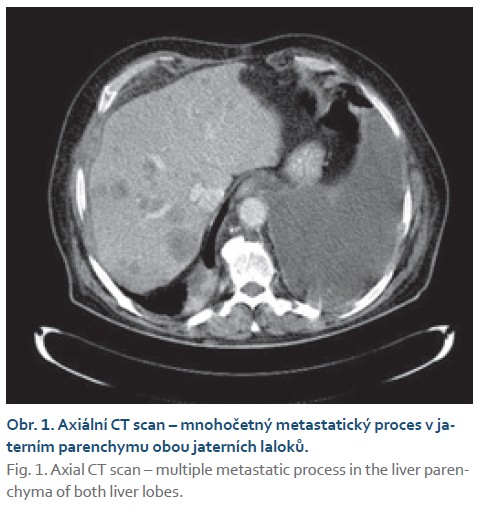

Rok po transplantaci (v únoru 2010) byl pacient hospitalizován k provedení protokolární jaterní biopsie, během níž byla na sonografii (USG) nalezena dvě ložiska v levém jaterním laloku. Bylo doplněno CT břicha (obr. 1, 2), kde byla ložiska popsána jako nejasná, se zvětšeným paketem uzlin retroaortálně, hlavním diagnostickým závěrem bylo podezření na přítomnost lymfomu. O pár dní později byl pacient přijat pro febrilie nejasné etiologie po necílené jaterní biopsii. Následně proběhla biopsie ložisek pod USG kontrolou a endosonografie, při které byla odebrána biopsie z retroaortálních lymfatických uzlin. Definitivním závěrem z histologicko-cytologického (cytoblok a cytologie) vyšetření byla přítomnost maligního melanomu. Od transplantace k diagnóze maligního melanomu uplynulo 395 dní. Pacient za hospitalizace podstoupil podrobné onkologické vyšetření (v dubnu 2010) a byla indikována terapie interferonem alfa, první aplikace proběhla bez komplikací. Během onkologické léčby byla pacientovi upravena imunosupresivní terapie (sirolimus 3 mg a mykofenolát mofetil 500 mg). V době léčby byla na USG přítomna v játrech dvě větší a řada menších ložisek (obr. 3). RTG snímek plic popisoval další suspektní ložiska v pravém horním plicním poli. Byla doplněna taktéž scintigrafie skeletu s nálezem osteolytických ložisek 8. a 9. žebra pravděpodobně metastatické etiologie.